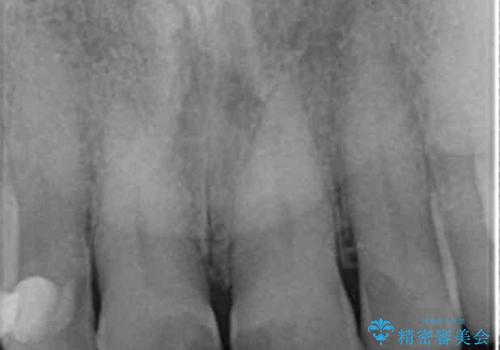

- 前歯の小さな虫歯を複数回治療した結果、つぎはぎだらけになってしまい審美的な改善を求めて来院されました。

これ以上のコンポジットレジン修復は更なる審美障害を招きかねないので、全体を覆うセラミッククラウンを選択します。

ディープバイト・噛み合わせが強いことからフルジルコニアクラウンを選択しました。